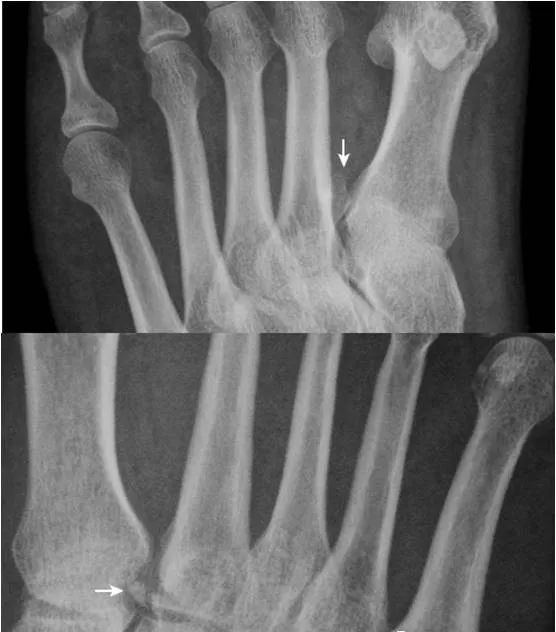

19.拇趾多分籽骨:

拇趾内外侧籽骨可表现为二分籽骨(箭)或三分籽骨(箭头),为正常变异,需与籽骨骨折、坏死鉴别。骨折边缘多不规则,坏死密度多不均。

22.趾骨骨骺:

拇趾远节趾骨骨骺内侧较外侧宽(箭),其与趾骨干骺端间距离较宽(箭头),为正常表现,勿误认为是骺离骨折。近节趾骨骨骺可呈扁平状,并密度增高,亦为正常表现,勿误认为坏死。

23.锥状骨骺:

第2~4近节趾骨骨骺呈锥状(箭),多由生长紊乱引起,是一种变异。同时可见拇趾近节趾骨骨骺密度增高(箭头)。